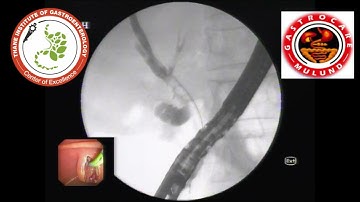

ERCP + BILIARY SPHINCTEROTOMY + MECHANICAL LITHOTRIPSY + CBD STONE EXTRACTION + STENTING